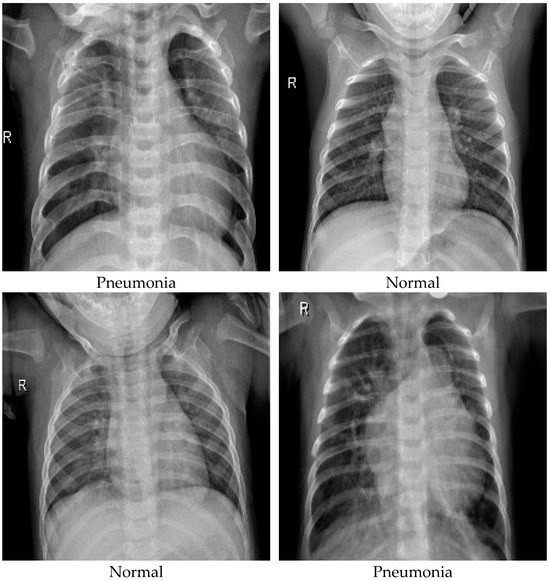

3.1. Data Overview

3.2. EDA and Preprocessing